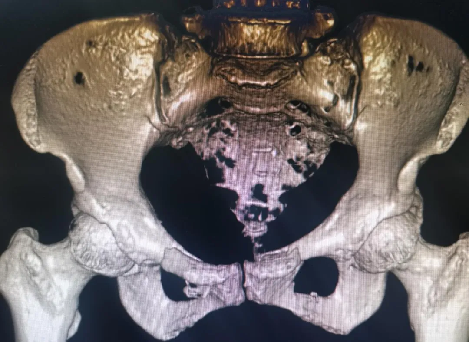

患者因外傷致骨盆前環骨折,患者難以忍(rěn)耐長期臥床及疼痛,要求(qiú)行手術治療以期早日自主翻身坐立活動。

案例三

創傷性骨盆骨折致尿道斷裂患者,膀胱(guāng)造瘺術後,需穩定骨折端(duān)避免二次傷害。

骨盆前環微創經皮內固定技術(INFIX技術)固(gù)定結合了內固定和外固定的優點,揚長(zhǎng)避短,針對此類(lèi)患(huàn)者,有效避免了術後深部感染,又避(bì)免(miǎn)了使(shǐ)用外固(gù)定的手術並發症,讓患者在最佳(jiā)治療時機獲得了骨盆環的穩定,並能早期開始功能鍛煉,最大程度上降低了因傷致殘的機(jī)率。